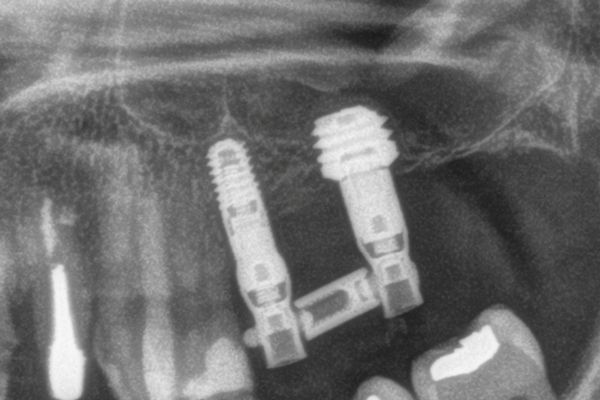

Implantes de 4,5mm de longitud utilizados en atrofia ósea en altura (hueso residual ≤ 4,5m). Estudio retrospectivo